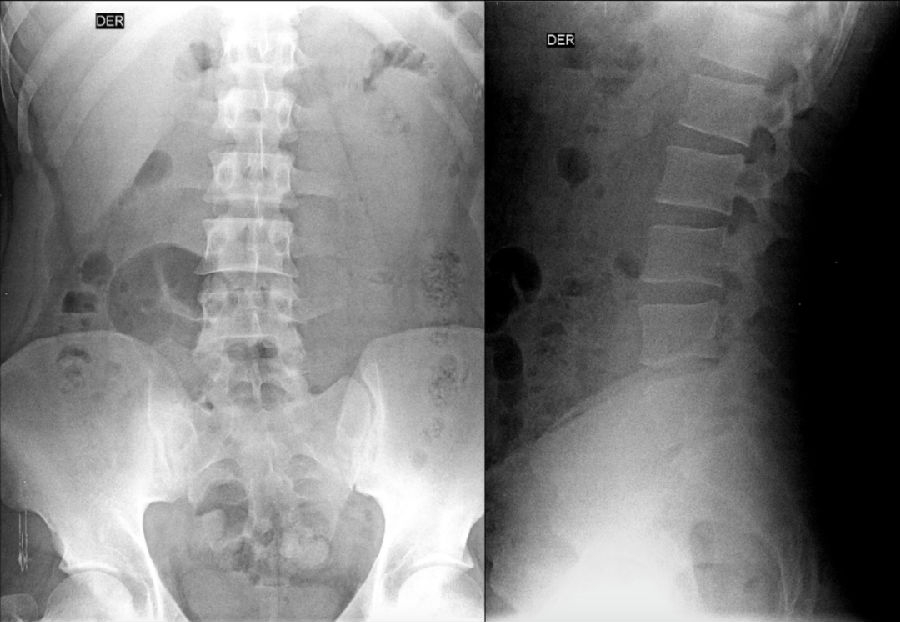

III型:单侧(IIIa)或双侧(IIIb)腰椎完全骶化,腰5横突与骶骨完全骨性融合

L5右侧横突肥大与骶骨发生骨性融合,为Ⅲa型

L5双侧横突与骶骨骨性融合,为Ⅲb型

IV型:一侧为II型即腰5横突与骶骨形成假关节,对侧为III型即腰5横突与骶骨形成骨性融合

IV型即混合型:L5双侧横突肥大,一侧与骶骨相接触为Ⅱ型表现,另一侧与骶骨形成骨性融合为Ⅲ型